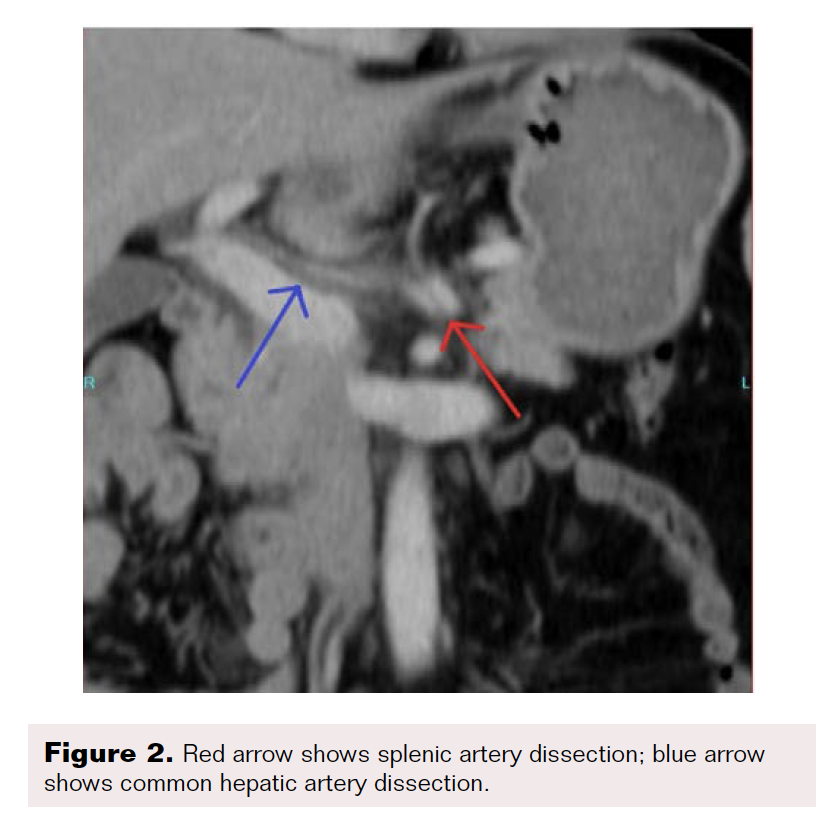

A contrast-enhanced CT scan was completed and revealed stenosis of the celiac trunk and mild bulbous dilatation of the post-stenotic celiac trunk (Figure 1). There was the appearance of a dissection flap that developed into an eccentric hypodense non-enhancing false lumen. This appeared to extend into the common hepatic arterial trunk and the splenic arterial branch, then continued to the splenic hilum (Figure 2 and Figure 3). In addition, there was a large splenic hypo-density involving almost one-third of the central spleen (Figure 4). The findings were consistent with an acute dissection of the splenic and hepatic arteries, along with splenic infarction of the central one-third of the spleen. A differential diagnosis of arcuate ligament syndrome was also considered, given the significant scoliosis seen on scout film of the CT scan (Figure 5).